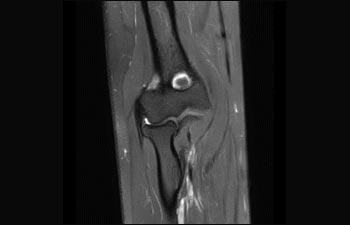

1 In base a uno studio interno in cui si confronta il flusso di lavoro con il sistema RM Achieva. 2 ComforTone sarà disponibile con Prodiva 1.5T a partire da fine 2017. 3 In base a uno studio interno che ha confrontato il flusso di lavoro di una serie di applicazioni su cervello, colonna vertebrale, apparato muscoloscheletrico e corpo con il sistema RM Achieva. 4 Per normale funzionamento si intende una scansione tipica eseguita in condizioni di disponibilità ininterrotta di elettricità, con raffreddamento del magnete e senza interventi di assistenza. 5 A seconda di quanto previsto nel contratto e della disponibilità locale. 6 "Altri" si riferisce a sistemi RM 1.5T da 60 cm per il corpo intero